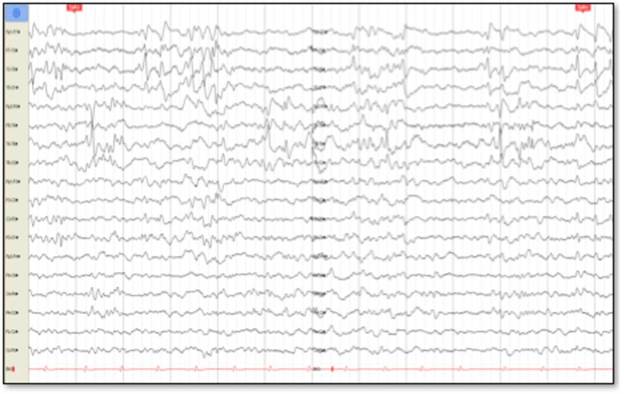

Cerebral nuclear magnetic resonance (NMR) showed generalized cortical atrophy and bilateral hippocampal atrophy (Figure 1), while electroencephalogram revealed independent bilateral temporal ictal activity, frequently associated with bradycardia and hypoxemia (Figure 2).

Electroencephalogram that reflects temporary, bilateral and independent epileptiform activity in the interjetai sleep records. November 2015.

Figure 2: Electroencephalogram that reflects temporary, bilateral and independent epileptiform activity in the interjetai sleep records. November 2015.

Source: Patient's studies. Image edited by the authors.